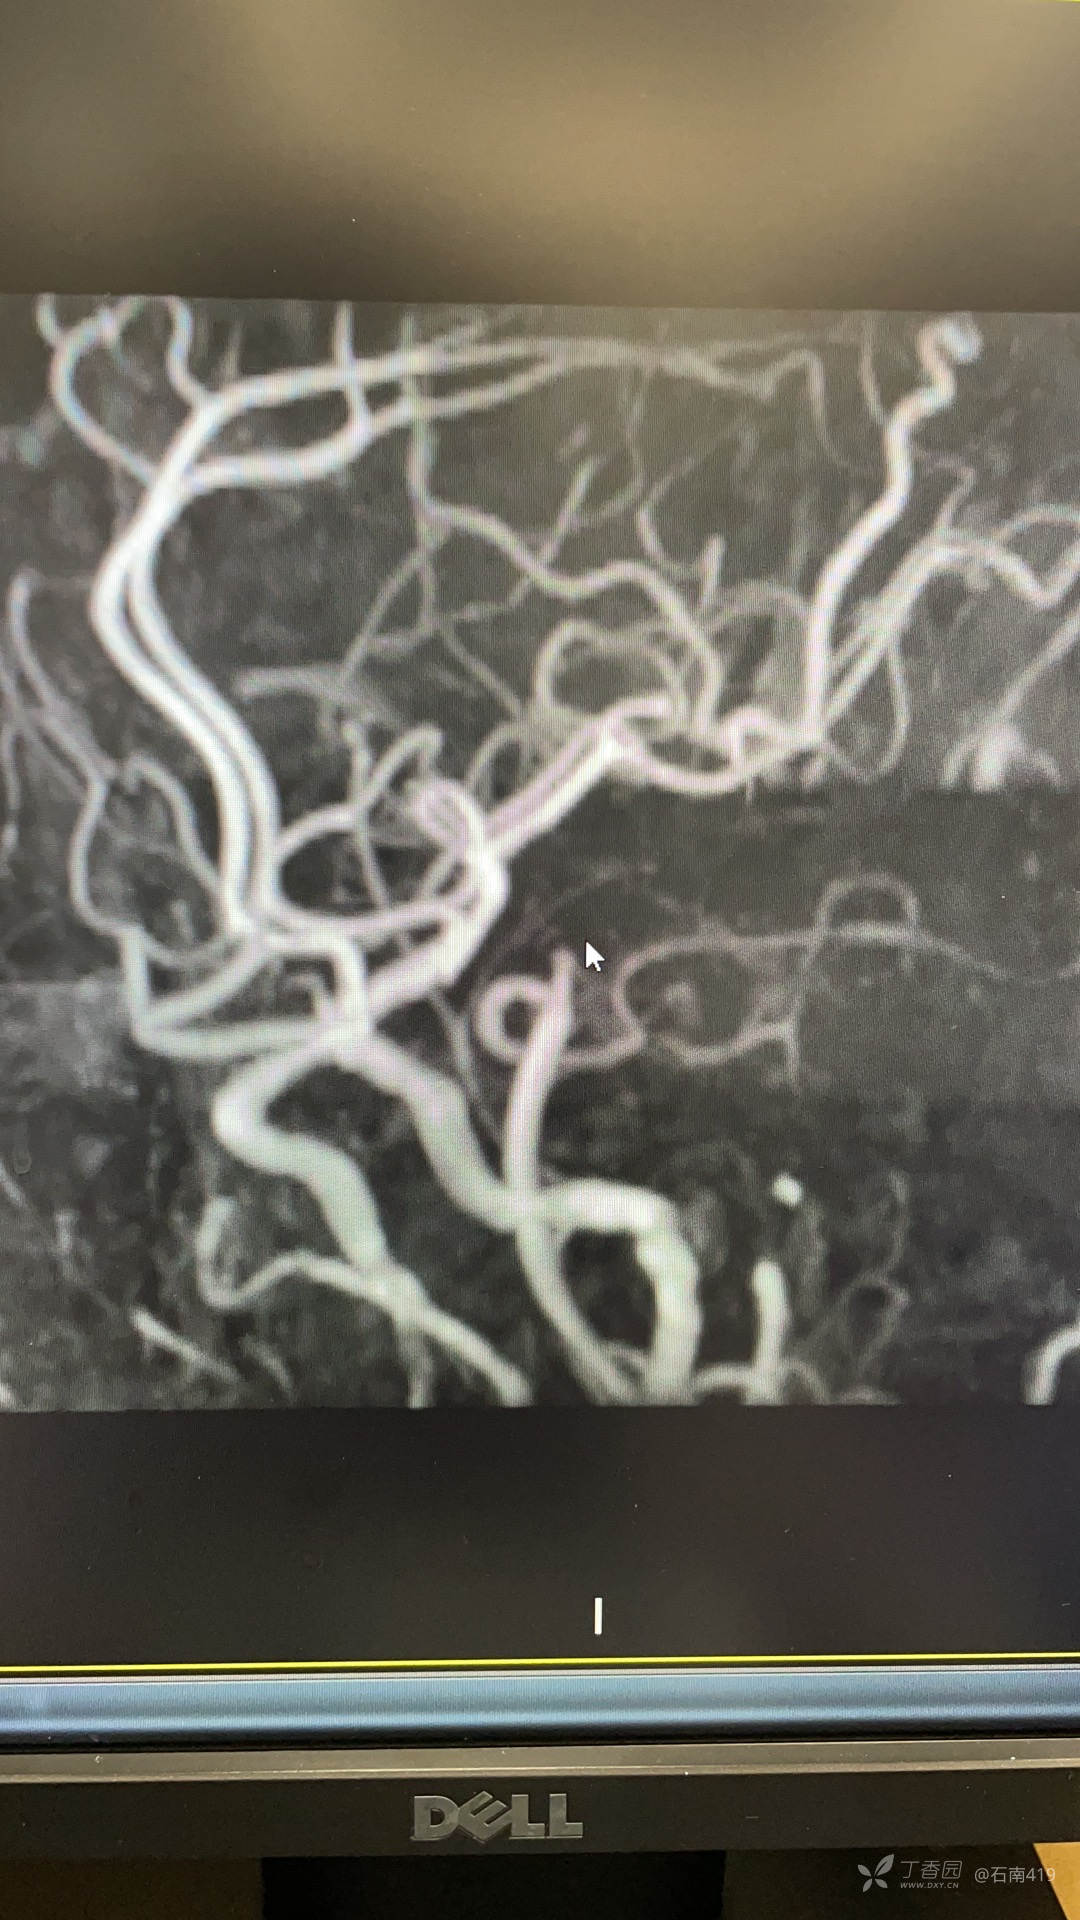

辅助检查:2022-01-31头颅MRI+DWI提示脑多发病损,急性脑梗死可能。